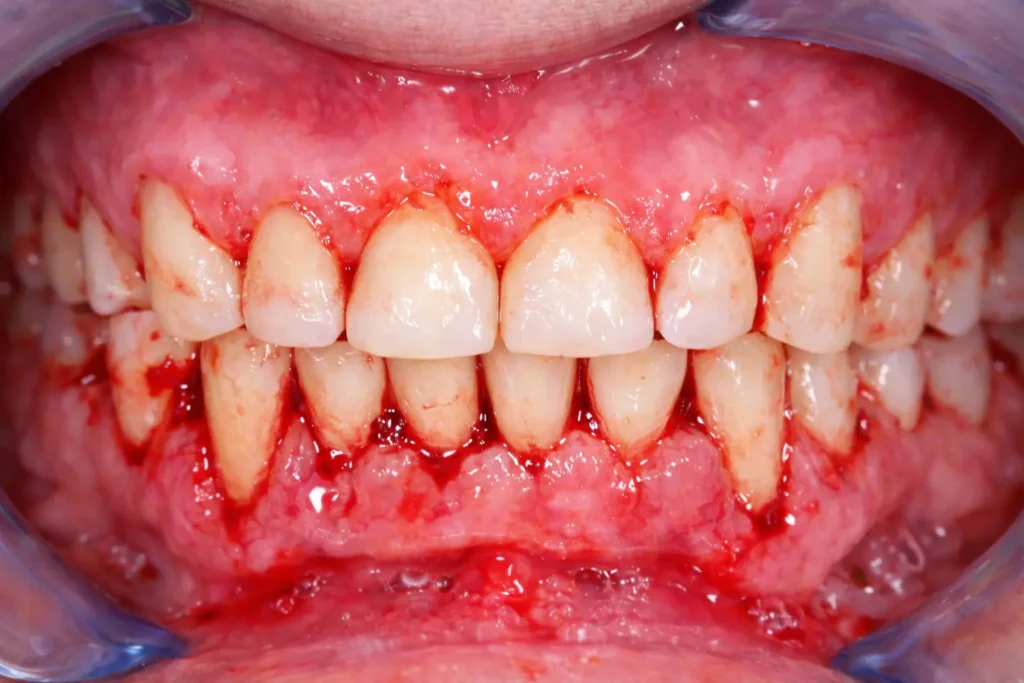

- Red, swollen gums

- Bleeding when brushing or flossing

- Mild tenderness

- Swollen, bleeding gums

- Frequent bleeding gums